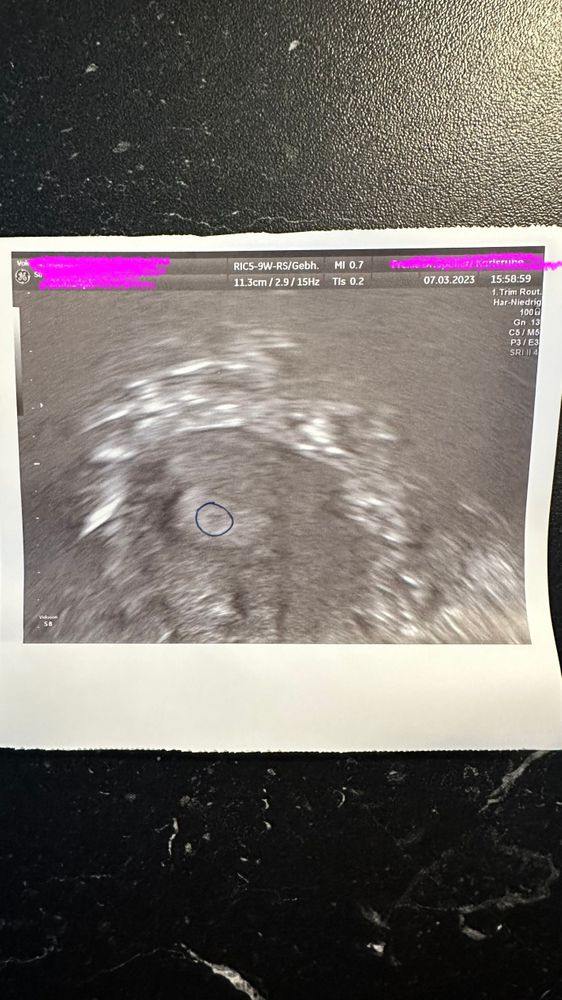

Девочки по акушерских неделях 6 ровно . Хгч 540 на узи в 5 недель и 3 дня увидели ели заметную точку . Ааа на меня я вообще не чего не увидела но врачу виднее . Сказали на узи через две недели и повторный анализ Хгч . Началась мазня также в 5 недель , выписали famenita 200 . Мажется 5 день . УЗИ через 5 дней не знаю что и думать

Виктория, сказали что на узи увидели беременность, я так вообще не увидела вообще ни чего , того он ручкой нарисовал то место где он это видел .

Hanna, честно говоря, я тоже там не вижу ПЯ(

Karmilla, так случилось потому что я поменяла врача . Первый взял анализ и второй через день . Сегодня была на приеме исключили внематочную. Взяли повторно анализы . Поехала к врачу и просто начала говорить что у меня стресс кровотечение не прекращаются, прописали мне двойную дозу прогестерона . На узи уже немного уже ярче точка. По срокам уже 6 недель а беременность сказал врач хорошая 50/50 . Может и вправду поздняя овуляция. У меня не очень стабильный цикл

Вот мое первое узи 7 .3 . Это не полных 6 недель . Позавчера была на узи а вчера пришли анализы Хгч